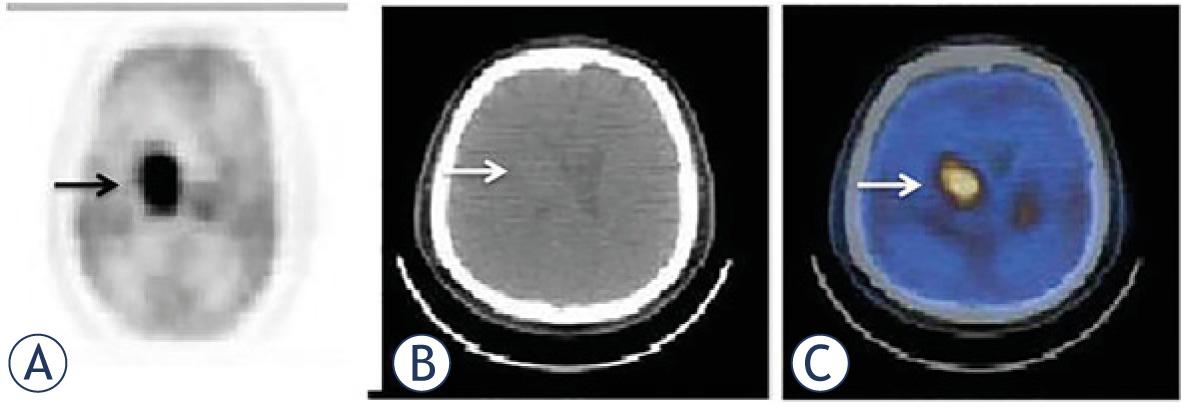

| 34 | 56 | F | DLBC | CNS | Corpus callosum | + | + | 19.2 | 10.4 | 43.9 | 456.4 | 8 | 58 |

| 35 | 31 | M | DLBC | CNS | Occipital lobe | + | + | 9.8 | 6.5 | 36.3 | 236 | 6 | 27 |

| 36 | 52 | F | MALT | CNS | R orbit | - | - | 3.1 | 2 | 5.6 | 11.2 | 119 | 119 |

| 37 | 49 | M | DLBC | CNS | Frontoparietal lobe;cerebellum | + | + | 16.2 | 8.9 | 183 | 1628.7 | 6 | 9 |

| 38 | 66 | F | DLBC | CNS | Parietooccipital lobe | + | - | 9.8 | 7.2 | 30.2 | 217.2 | 9 | 30 |

| 39 | 64 | M | MC | CNS | R orbit | + | - | 3.7 | 2.9 | 2.6 | 7.45 | 19 | 38 |

| 40 | 40 | F | DLBC | CNS | Cerebellum | + | - | 17.5 | 10.5 | 10 | 105 | 3 | 7 |

| 41 | 66 | M | MALT | CNS | R orbit | - | - | 5.8 | 3.8 | 1.95 | 7.4 | 33 | 33 |

| 42 | 45 | M | DLBC | CNS | Occipital lobe; cerebellum | + | + | 22.3 | 12.4 | 63.3 | 782.2 | 3 | 3 |

| 43 | 60 | M | MALT | CNS | L orbit | - | - | 7.1 | 4.5 | 2.6 | 11.8 | 36 | 36 |

| 44 | 34 | F | DLBC | CNS | Cerebellum; lateral ventricle | + | + | 15.6 | 8.2 | 21.8 | 180.1 | 9 | 11 |